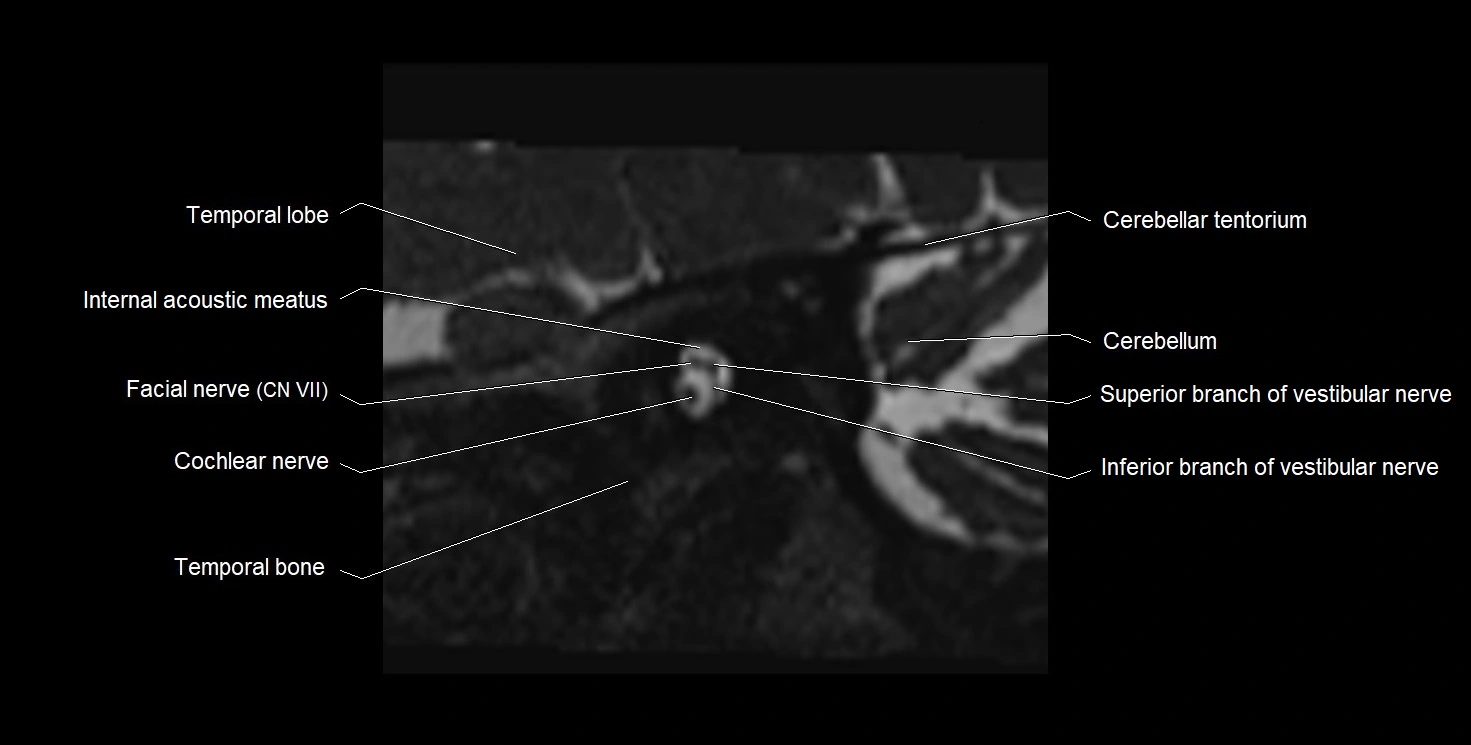

MRI Appearance

• The abducens nerve is a small, thin, linear structure

• Best visualized on high-resolution T2-weighted 3D MRI sequences (e.g., FIESTA or CISS)

• Seen as a hypointense (dark) line running from the brainstem at the pontomedullary junction, traversing the prepontine cistern, and entering Dorello’s canal under the petrosphenoidal ligament, then into the cavernous sinus, and finally the orbit

• May be challenging to visualize in standard MRI due to its small size

• Pathology may be inferred by absence, displacement, or enhancement of the nerve